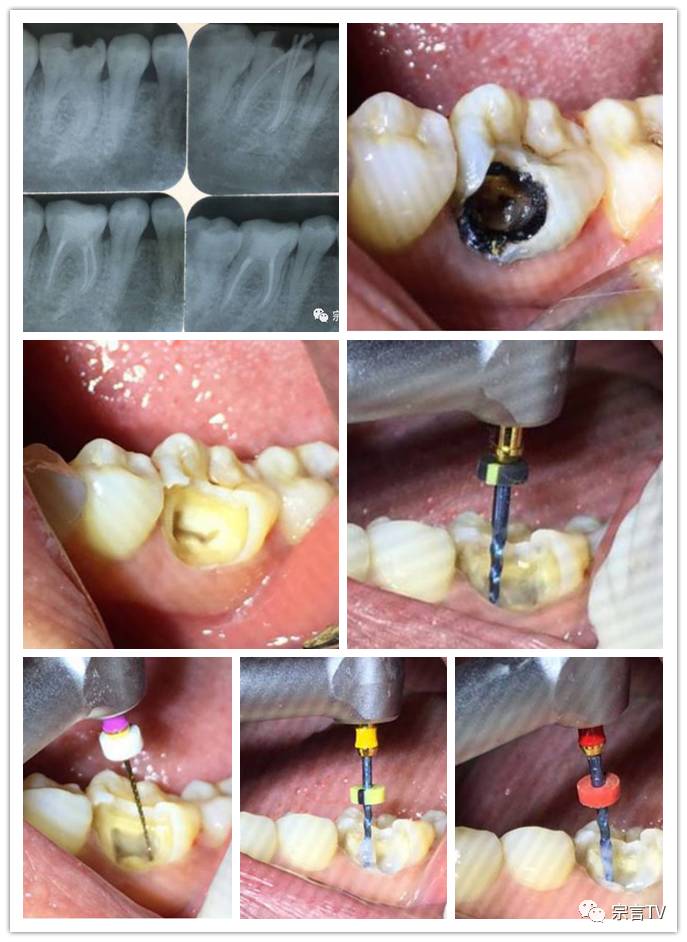

根管锉在临床中的应用与剖析于洪涛老师

如何进行规范化根管治疗?

在这里,将为大家一一解读。导读:本期课程主要详细讲解根管治疗的规范化操作,现场有真人病例操作展示。除此之外,还为大家解说根管治疗后期常见的问题及应对方法。

根管治疗修复的全过程(真人临床操作)